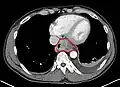

Additional testing is needed to assess how much the cancer has spread (see § Staging, below). Computed tomography (CT) of the chest, abdomen and pelvis can evaluate whether the cancer has spread to adjacent tissues or distant organs (especially liver and lymph nodes). The sensitivity of a CT scan is limited by its ability to detect masses (e.g. enlarged lymph nodes or involved organs) generally larger than 1 cm.[44][45] Positron emission tomography is also used to estimate the extent of the disease and is regarded as more precise than CT alone.[46] PET/MR as a novel modality has shown promising results in preoperative staging with fair feasibility and good correlation in comparison to PET/CT. It can enhance tissue differentiation with lowering the radiation dose to the patient.[47] Esophageal endoscopic ultrasound can provide staging information regarding the level of tumor invasion, and possible spread to regional lymph nodes.

Contrast CT scan showing an esophageal tumor (axial view)

Contrast CT scan showing an esophageal tumor (coronal view)